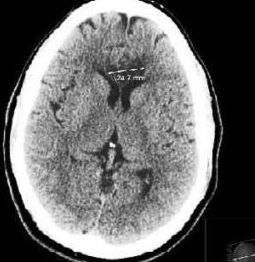

A 47-year-old man with hypertension, hyperlipidemia, and chronic cocaine and alcohol abuse presented with right-sided weakness and numbness. A CT brain scan showed a left anterior cerebral artery ischemic stroke. A second scan showed a bilateral corpus callosum lesion.

Hypertension at midlife is associated with white matter damage, a pathologic process usually expected later in life. Plaque deposition, lacunar infarcts, and small bleeds are a consequence of hypertension, which can cause progressive atrophy of the neocortex, hippocampus, and amygdala without clinical evidence for a stroke and has more subtle effects. All of these factors contribute to dementia in hypertensive patients. And diabetes makes the injuries even worse.

Medicine has described blood pressure as the culprit in cerebrovascular disease manifesting as strokes, with a focus on the combination of blood pressure and strokes as an “older person’s” problem. However, the damage is occurring in typical middle-aged persons with hypertension who come to primary care offices every day.